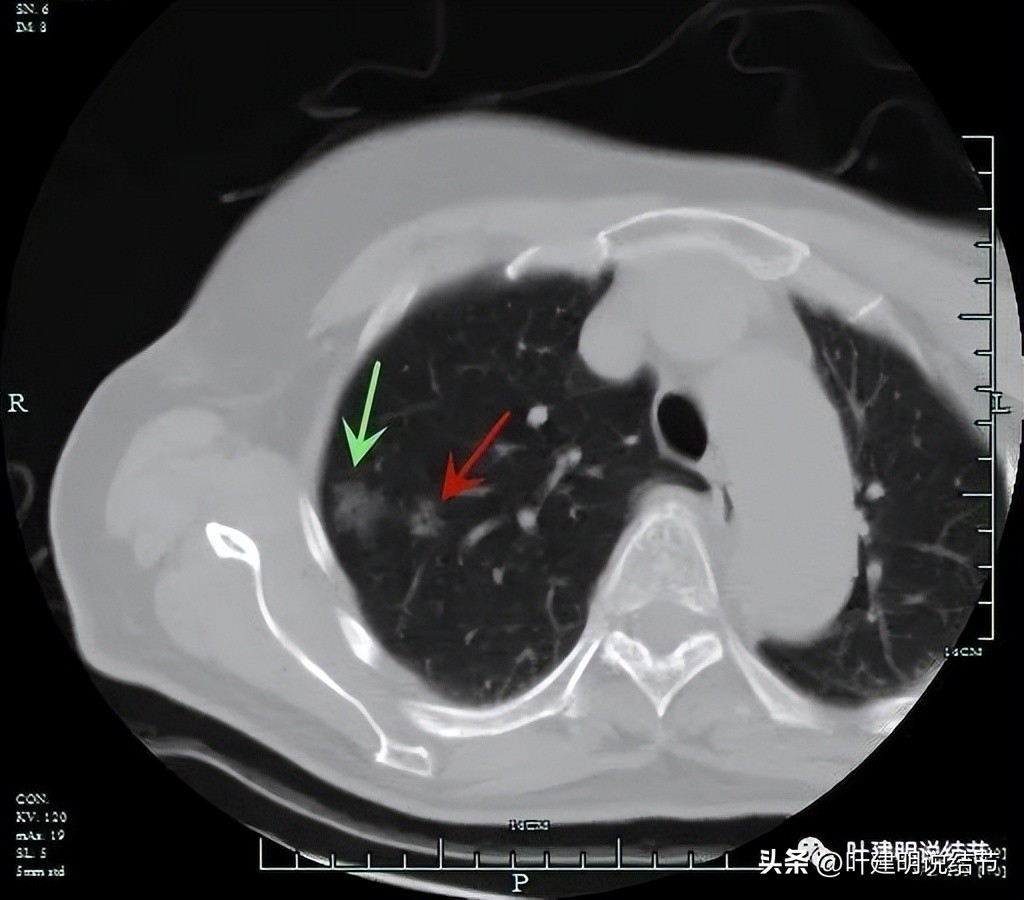

非薄层扫描显露右上叶略显模糊的磨玻璃结节,中间有小空泡的样子,边缘不平显得有毛刺样征,密度不均匀。

薄层显示病灶磨玻璃密度,内部有血管穿行,灶内有小空泡的样子,整体边缘轮廓较清。

灶内穿行的血管有异常增粗,且显得毛糙。灶内空泡样征是扩张的细支气管;表面不平,似有浅分叶的样子。磨玻璃部分密度较低。

靶扫描重建发现病灶内部穿行血管毛糙,细支气管扩张,边缘毛刺样征。

此灶虽然瘤肺边界显得不如典型的那些磨玻璃结节是肿瘤的清楚,但它整体轮廓仍然较清,而且发现随访3年无吸收好转,显然不会是普通炎症的。再加上密度欠均、灶内细支气管扩张、血管进入与穿行、血管入病灶后散开来,整体显得有些僵硬,肯定是要考虑肿瘤范畴的。从密度来看,磨玻璃部分密度较低,似不典型增生的密度,但因有血管进入并异常增粗,考虑要升级,而原位癌的密度一般要略高一点,所以该考虑微浸润性腺癌可能性大,并不能完全除外浸润性腺癌,贴壁为主型。